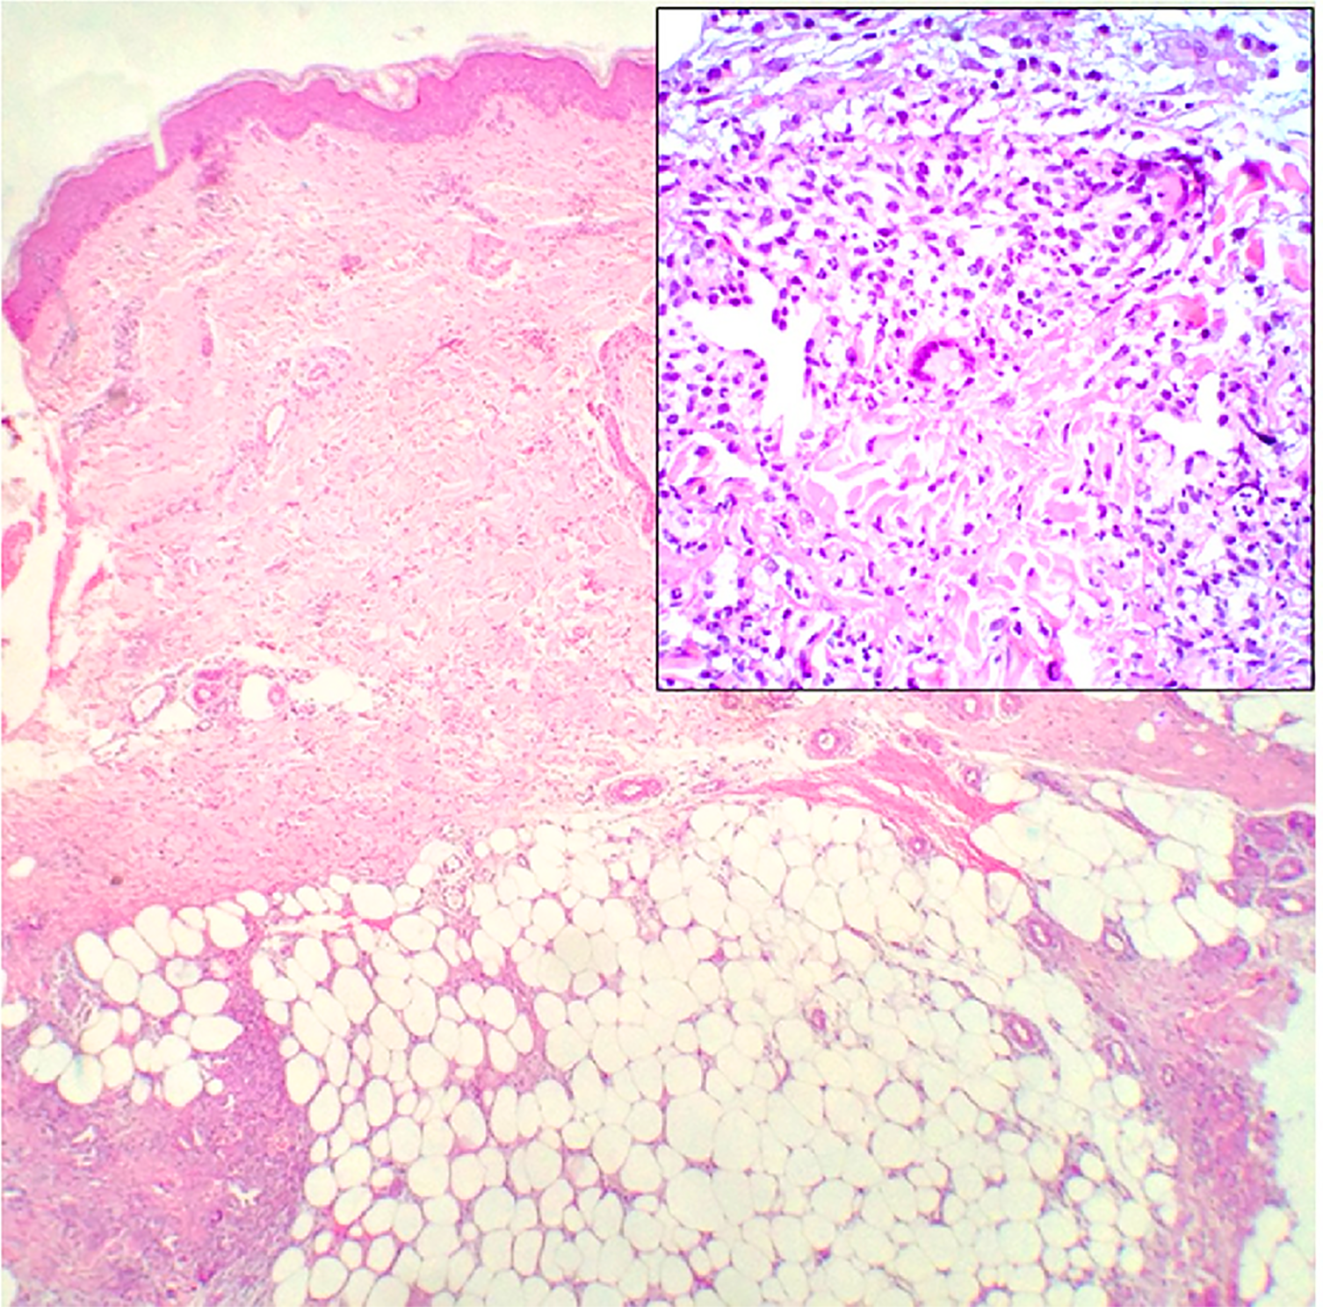

The histopathologic features of PG are not specific (Figure 3). They can be explained by the chronology of lesions and one relies on the site of the biopsy (64). Early lesions present as deep perifollicular inflammation with a dense lymphocytic infiltration (64, 65). Ulceration of the epidermis is often secondary to inflammation of the dermis (64), and their centers show sterile purulent dermatitis and panniculitis with numerous infiltrations of macrophages and multinucleated histiocytes (66). Inflammatory cell infiltration, predominantly by lymphocytes, is often reported in the surrounding skin (64, 66). Biopsies of later-stage ulcers show a dense neutrophilic infiltrate with features of abscess formation (64). As the lesion regresses, plasma cells and macrophages intrude the dermis, and eventually, the inflammation is replaced by fibrosis (66).

Figure 3 Histopathology of ulcerative PG. (A) Low-power magnification (H&E staining, ×125) reveals diffuse epidermal necrotic ulcer with massive neutrophilic infiltrations and dermal granulation tissue. (B) High-power magnification (H&E staining, ×2000) demonstrates that the majority of lesional cells consist of neutrophils. Reproduced with permission from (62). © 2023 Indian Journal of Dermatology, Venereology and Leprology - Published by Scientific Scholar.